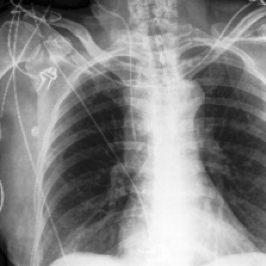

Waterbirds (Sagawa et al., 2020) is an image classification dataset where bird types are associated with a spurious background attribute (water or land). CelebA (Liu et al., 2015) is an image classification dataset, where hair color is an imbalanced attribute with respect to gender. MultiNLI (Williams et al., 2018) is a text benchmark of categorizing two sentences as entailing each other, contradicting each other, or neutral. The spurious correlation is between negation words like “never” and the “contradiction” label. CivilComments (Borkan et al., 2019) is a toxicity text classification dataset containing underrepresented demographic groups. CheXpert (Irvin et al., 2019) is a large-scale medical dataset of chest radiographs with rare pathologies, especially amongst certain minority groups.